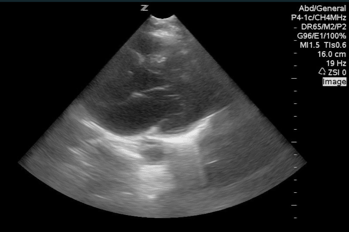

QA of the Day: PSL view and can just make out a massively dilated aortic root! #pocus #foamed #foamus